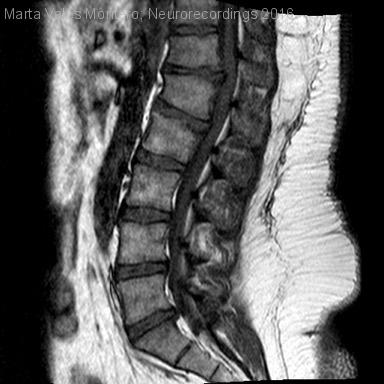

Hombre | 20 años

Diagnóstico final: Síndrome de cono medular secundario a hernia discal

Varón de 20 años de edad con obesidad mórbida que consulta por alteración sensitiva en miembros inferiores de un mes de evolución. Al inicio presentaba dolor lumbar no irradiado asociado a sensación de hormigueo en...